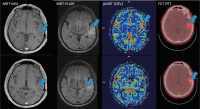

Abbildung 2: MRT (KM/FLAIR/pMRT) und FET-PET vom September 2013. Leichte KM-Aufnahme, zunehmende T2-hyperintense Läsion, sowie beginnende Hyperperfusion in der pMRT (CBV), als indirekte Zeichen einer Malignisierung. Ebenso in der FET-PET-Untersuchung vermehrter Tracer-Uptake links-temporal (Tumorbereich mit Pfeil markiert)